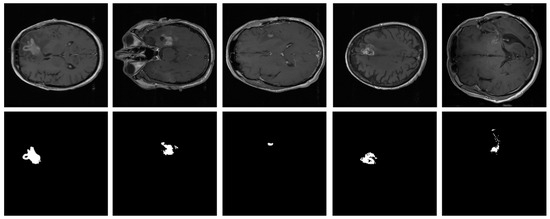

- This study proposes a robust CAD framework based on radiomic parallel features aggregation for the accurate segmentation of three different BT regions. The framework comprises an encoder–decoder architecture, with a novel PFA block comprising multiple-branch feature extraction layers to learn discriminative information from the BT scans in parallel and aggregate them.

- In the encoder module, the PFA block is integrated at low, intermediate, and high levels to capture a comprehensive representation of the BT and preserve diverse multi-level information throughout the encoding process. The multi-level aggregated features capture the overall characteristics of the BT, incorporating local details, such as small tumor boundaries, particularly for ET, intermediate-level structures, such as the shape of the BT, and high-level global information, such as the overall location and size of the BT.

- In contrast to the encoder module, the decoder module utilizes the PFA block to collectively process upscaled low-level, intermediate-level, and high-level bottleneck-rich semantic features in parallel. Subsequently, the PFA block aggregates these semantic features to ensure that the decoder module has access to a diverse range of information, including fine-grained details and high-level contexts.

- Our proposed PFA-Net surpasses the state-of-the-art methods in the field of heterogeneous dataset analysis in terms of segmentation performance and computational efficiency, with 19.49 million (M) parameters less than those of the previous method.